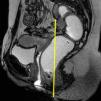

Las secuencias FSE T2 son útiles para evaluar posibles alteraciones musculares, como adelgazamiento o desgarros, en especial del músculo puborrectal (fig. 5). La serie axial debe planificarse en paralelo al propio puborrectal (línea H), desde el ano hasta un nivel superior al sigma. La serie coronal debe planificarse en perpendicular al puborrectal, desde la sínfisis púbica hasta el coxis (fig. 6).

Las secuencias dinámicas FIESTA se componen de múltiples imágenes de un mismo plano (multifase), obtenidas principalmente durante la realización de esfuerzos y cuya posterior visualización en sucesión rápida muestra el movimiento del contenido pélvico. Este tipo de secuencia permite obtener imágenes nítidas de las estructuras en movimiento, ya que cada imagen se obtiene en décimas de segundo (emplear la opción array spacial sensivity encoding technique [ASSET] contribuye a acelerar la adquisición). En nuestro protocolo obtenemos una serie coronal de 50 imágenes durante maniobra de Valsalva planificada sobre el canal rectal, útil para observar posibles rectoceles laterales (fig. 7). Obtenemos asimismo varias series de 120 imágenes de un plano sagital medio de la pelvis, centrado sobre el eje largo del canal rectal y cortando el cérvix (fig. 8). Es importante mantener esta orientación —salvo que el cérvix se encuentre desplazado lateralmente en exceso— para que este no quede fuera de plano y pueda visualizarse correctamente un posible descenso. Esta serie se realiza 4 veces: en reposo, con maniobra de contención, en maniobra de Valsalva y mientras el paciente tose. Finalmente, durante la evacuación, obtenemos una serie similar con 250 imágenes. Al tratarse de maniobras que conllevan presión abdominal, pretende observarse la respuesta del contenido pélvico ante tal presión. La serie adquirida durante la evacuación muestra además la función del músculo puborrectal, el recto y el canal anal. Si se produce una evacuación incompleta, es conveniente realizar una segunda serie. En el caso de las mujeres, puede valorarse si es necesario que la paciente realice una digitación intravaginal para favorecer la evacuación definitiva.